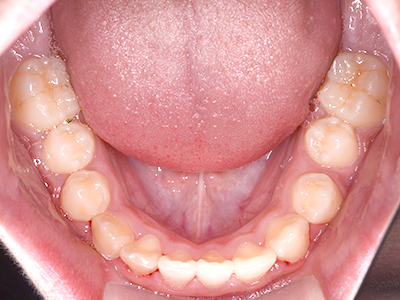

歯並びの相談に来られるお子様は、口呼吸をしているケースが多く、これが歯並びに大きな影響を与えています。

↓ - 上あごが狭くなる

↓ - 下あごが狭くなる・下あごの位置が悪くなる

↓ - さまざまな不正咬合が生じる

ないき歯科クリニックでは、上あごの成長不足を補い、鼻呼吸を獲得しつつ歯列を整え、将来のお口をより健康な状態にすることをゴールに定める矯正治療をおこなっています。